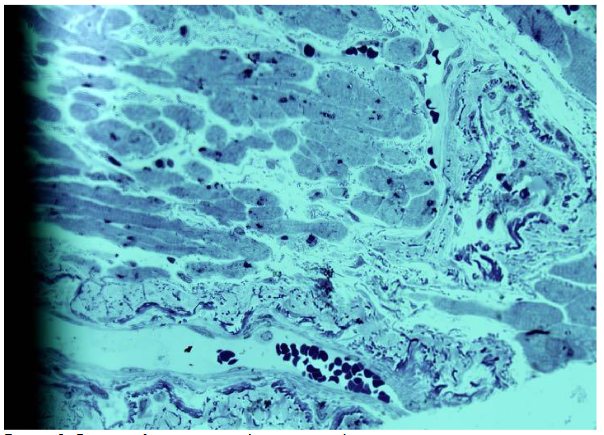

Semithin epoxy slices with up to 1 micrometer thickness were prepared using an Ultracut Riechert. Sections were stained with 1% solution of Azur II by special method and examined under a light microscope using a 40× objective lens combined with a 10× ocular lens.

On semithin epoxy sections stained with Azure-2, images of arterioles from the right atrial appendage were obtained. Six male patients with CAD, aged 48 to 65 years, were included in the study. To obtain a reliable representation of pathological changes in the arterioles, the entire biopsy material was utilized. Very small myocardial fragments of the atrial appendage were processed and embedded in epoxy resin, resulting in up to eight gelatin blocks.

The obtained images of arterioles were characteristic for each individual patient, showing both similarities and differences. The arterioles displayed variable lumen diameters, ranging from very large to small profiles. Wall thickness also varied, with some arterioles showing pronounced intussusceptive invaginations into the lumen. In certain cases, bridges connecting opposite arteriolar walls were observed, sometimes multiple in a single vessel.

Atherosclerotic changes were particularly notable in larger arterioles. These vessels exhibited elongated lumens, significant wall thickening, and abundant smooth muscle cells. Some large arterioles showed up to two convolutions at different ends of the lumen. Evidence of newly forming arterioles was observed, including residual fragments indicating separation. Notably, the newly separated arterioles differed markedly in lumen size compared to the parent vessel. In some separated segments, chambers were present, indicating the formation of a new convoluted vessel.

Frequently, arterioles with thickened walls consisted of multiple aligned lumens of different sizes, suggesting formation through bridging of opposite walls.